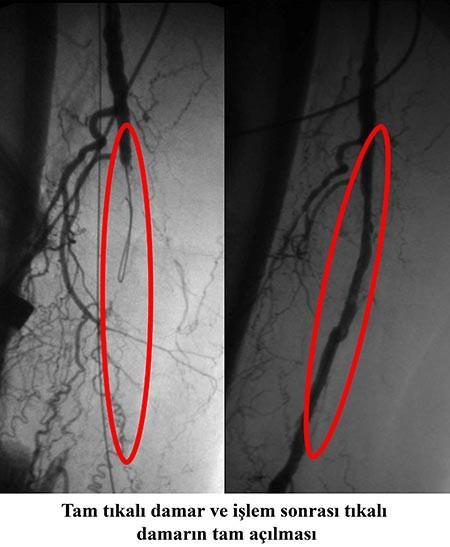

Kalp damarı açma. Ana sayfa tıkalı damarı balonla açma. Profdrahmet maranki kalp ve damar sağlığı ve damar tıkanıklığını gidermek için alıç çayı kürünü öneriyor kalp ve damar sağlığını korumak ve tıkalı kalp damarlarını açan alıç çayı hazırlamak için 1 su bardağı kaynar suyun içine 1 tatlı kaşığı kırmızı alıcın yaprak çiçek ve meyvelerinden koyduktan sonra bir kaç dakika kısık ateşte demlendirin. Kalp kapak hastalıkları. 58 yaşında yürümekle ciddi sol bacak ağrısı olan hastanın yapılan mr anjiyoda sol bacak damarının uzun segment 30 cm kadar tamamen tıkalı olduğu gözlendi.

Türkiye den amerika ya tam tıkalı damar açma dersi türk kardiyolog prof. Her operasyonda olduğu gibi komplikasyonlar gelişebilir bu risklere girmeden hayatımıza sporu sokarak hem damar ve kalp sağlığımızı. Cevdet koçoğulları bu şekilde ameliyat ettiği hastaların kısa sürede normal. Son teknoloji ile tıkalı damarı açma yöntemi.